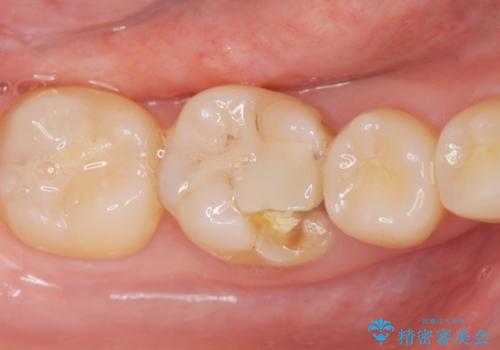

レントゲンで見つかった歯と歯の間の虫歯をセラミックインレーで修復

- e-maxインレー 7.7万円 費用は治療当時の料金となります

e-max(セラミック)の治療は劣化をせず、歯質との隙間もできないため虫歯の再発のリスクが低いです。